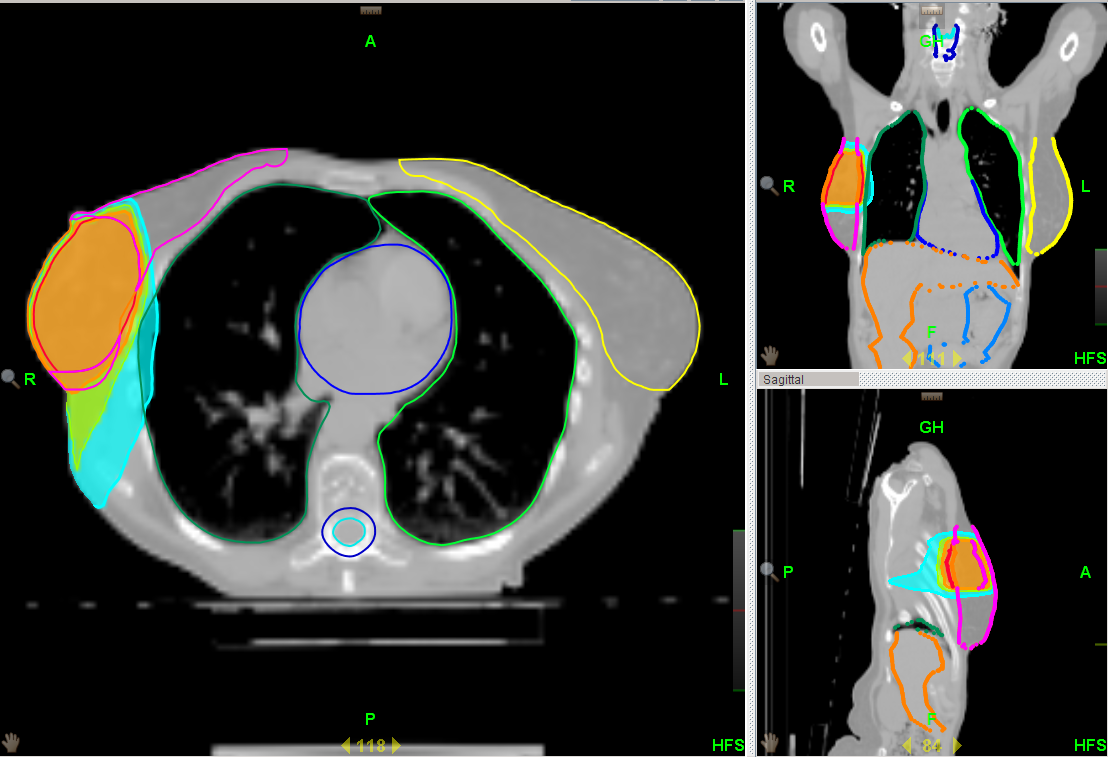

PBI, Partial breast irradiation (irradiazione parziale della mammella): Per pazienti selezionate in base alle linee guida nazionali ed internazionali, la Divisione di Radioterapia propone l’irradiazione parziale del seno operato con radioterapia a fasci esterni. Le dimensioni limitate del campo di radioterapia e l’utilizzo della intensità modulata (IMRT) consentono di risparmiare i tessuti sani circostanti e il trattamento può essere eseguito in una settimana solo (fig. 2).

| Fig. 1 | Fig. 2 |